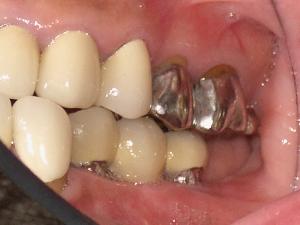

STEP6 上部構造の設置

STEP7 上部構造のチェック